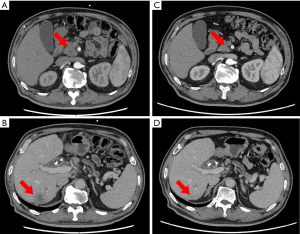

A 59-year-old man presented with a 1-month history of abdominal distension as well as jaundice of the skin and sclera for 18 days. He had a 10-year history of diabetes mellitus and hypertension. He had abnormally high concentrations of biomarkers of liver tumors and function (CA19-9, 264.1 U/L; CEA, 8.0 U/L; alanine aminotransferase, 144 IU/L total bilirubin, 415 µmol/L; and direct bilirubin, 223 µmol/L). Magnetic resonance cholangiopancreatography (MRCP) revealed bile duct dilatation and a mass at the head of the pancreas. Enhanced CT detected a metastatic lesion in the right lobe of the liver (Figure 4). Endoscopic ultrasonography-guided biopsy confirmed the diagnosis of pancreatic adenocarcinoma. Percutaneous transhepatic cholangio drainage was then performed to reduce jaundice, which was followed by five cycles of FOLFIRINOX. During the second cycle of chemotherapy, a grade-3 adverse event (febrile neutropenia) occurred. Therefore, the remaining three treatment cycles used an 80% dose of FOLFIRINOX. After chemotherapy concluded, enhanced CT revealed obvious reduction of the pancreatic and liver lesions (Figure 4). The patient subsequently underwent pancreaticoduodenectomy, during which intraoperative brightness mode ultrasound did not detect suspicious liver lesions. Histopathology, which revealed a PDAC that exhibited intermediate differentiation, detected two of 31 regional lymph nodes with metastasis. After operation the patient accepted six cycles of FOLFIRINOX treatment and was alive 12 months after diagnosis without detectable recurrence.

A 65-year-old man presented with a 5-day history of abdominal distension. MRCP and enhanced CT showed a mass located at the head of the pancreas. Endoscopic ultrasonography-guided biopsy confirmed the diagnosis of pancreatic adenocarcinoma, and Pancreaticoduodenectomy was subsequently performed. Histopathology showed a PDAC with intermediate differentiation but did not detect regional lymph node metastasis (0/19). After surgery, the patient received two cycles of gemcitabine combined with capecitabine. However, his high CA19-9 concentration persisted, and PET-CT detected tumor recurrence at the region of bilioenteric anastomosis and the fifth segment of the liver. PET-CT showed a mass with high metabolic activity at the anastomotic biliary-intestinal region and segment 5 of the liver. Therefore, we switched to FOLFIRINOX treatment. The patient’s CA19-9 concentration decreased more than 2-fold after six cycle of FOLFIRINOX treatment (Figure 5). This patient abandoned further chemotherapy after nine cycle of FOLFIRINOX treatment and got multiple liver metastasis. He was alive 14 months since diagnosed.